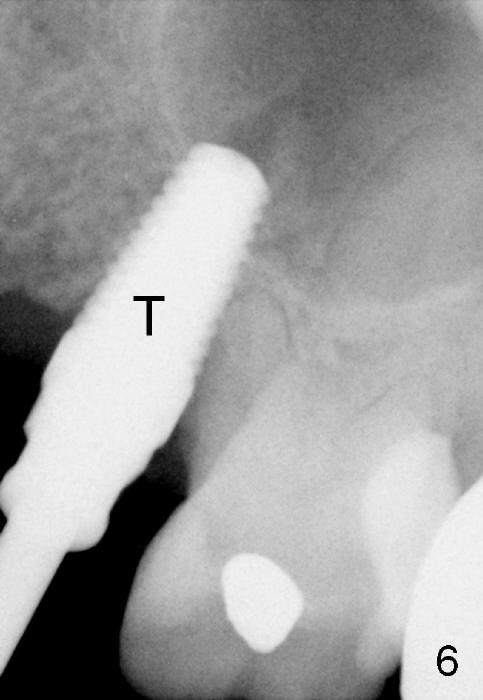

The anterior retainer is kept as a crown at #11 (Fig.2: C), whereas the residual root at the site of #13 is extracted with apical perforation (Fig.3 ^). It is confirmed by Fig.4 (<). To close the perforation, an osteotomy is initiated on the palatal wall of the socket with a 2 mm osteotome (Fig.5 insert: circle). As the osteotomy is being enlarged by a 3 mm osteotome, the bone between the original socket and the osteotomy is being pushed buccally. The former is being closed (Fig.5). The osteotomy is finished with combination of osteotomes and reamers. Fig.6 shows that a 5x14 mm tap is inserted at the site of #13 and that the sinus floor is lifted. In fact the sinus membrane is partially torn at the osteotomy, which is repaired by insertion of Colla-form Dressing (Impladent), followed by autogenous bone (harvested from reamers) mixed with Osteogen (Impladent). A 5x14 mm implant is placed at the site of #13 with insertion torque more than 60 Ncm (Fig.7: I). An incision is made at the site of #12 to start osteotomy with insertion of a parallel pin (Fig.7 P). A 3 mm reamer is kept in place for position confirmation (Fig.8 R). Due to ridge atrophy (Fig.2 arrowheads), a much smaller, but longer implant is placed at the site of #12 (Fig.9: 4x17 mm). The autogenous bone harvested from #12 osteotomy is placed in the buccal gap of #13, followed by insertion of Colla-form Dressing (Fig.10 M). To protect the membrane, a short abutment (4x3 mm) is temporarily placed (Fig.9,10 A) and perio dressing (Fig.9 D) is applied around the abutment and the interproximal areas of the neighboring teeth. Usually perio dressing dislodges around 1 week postop, particularly for a large edentulous space. In this case, the dressing is quite stable 11 days postop: the abutment (Fig.11 A) appears to contribute to retention of the dressing (D).